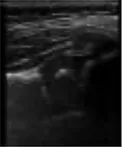

In this study, the GE LOGIQ-E9 ultrasonic diagnostic instrument (America) and 9l linear probe with a frequency range of 5.0–9.0 MHz were employed for imaging of the hip joint. The ultrasound coronal plane of Graf’s method was chosen as the standard imaging technique for this purpose. The imaging procedures were conducted by experienced senior physicians who possess the necessary expertise and technical skills in ultrasound imaging. In the standard imaging, four markers were identified, namely the iliac bone, bony rim point, lower iliac limb point, and glenoid labrum, as illustrated in Figure 2. These markers were selected based on their ability to provide accurate and reliable measurements of the hip joint. The utilization of a standardized imaging protocol and the identification of these markers allowed for consistent and reproducible imaging of the hip joint, ensuring the validity and reliability of the data obtained in this study.

FIGURE 2

www.frontiersin.org

Figure 2. Measurement of the neutral coronal plane of the hip joint using the graf method. (A) Iliac bone, (B) bony rim point, (C) lower iliac limb point, (D) glenoid labrum.